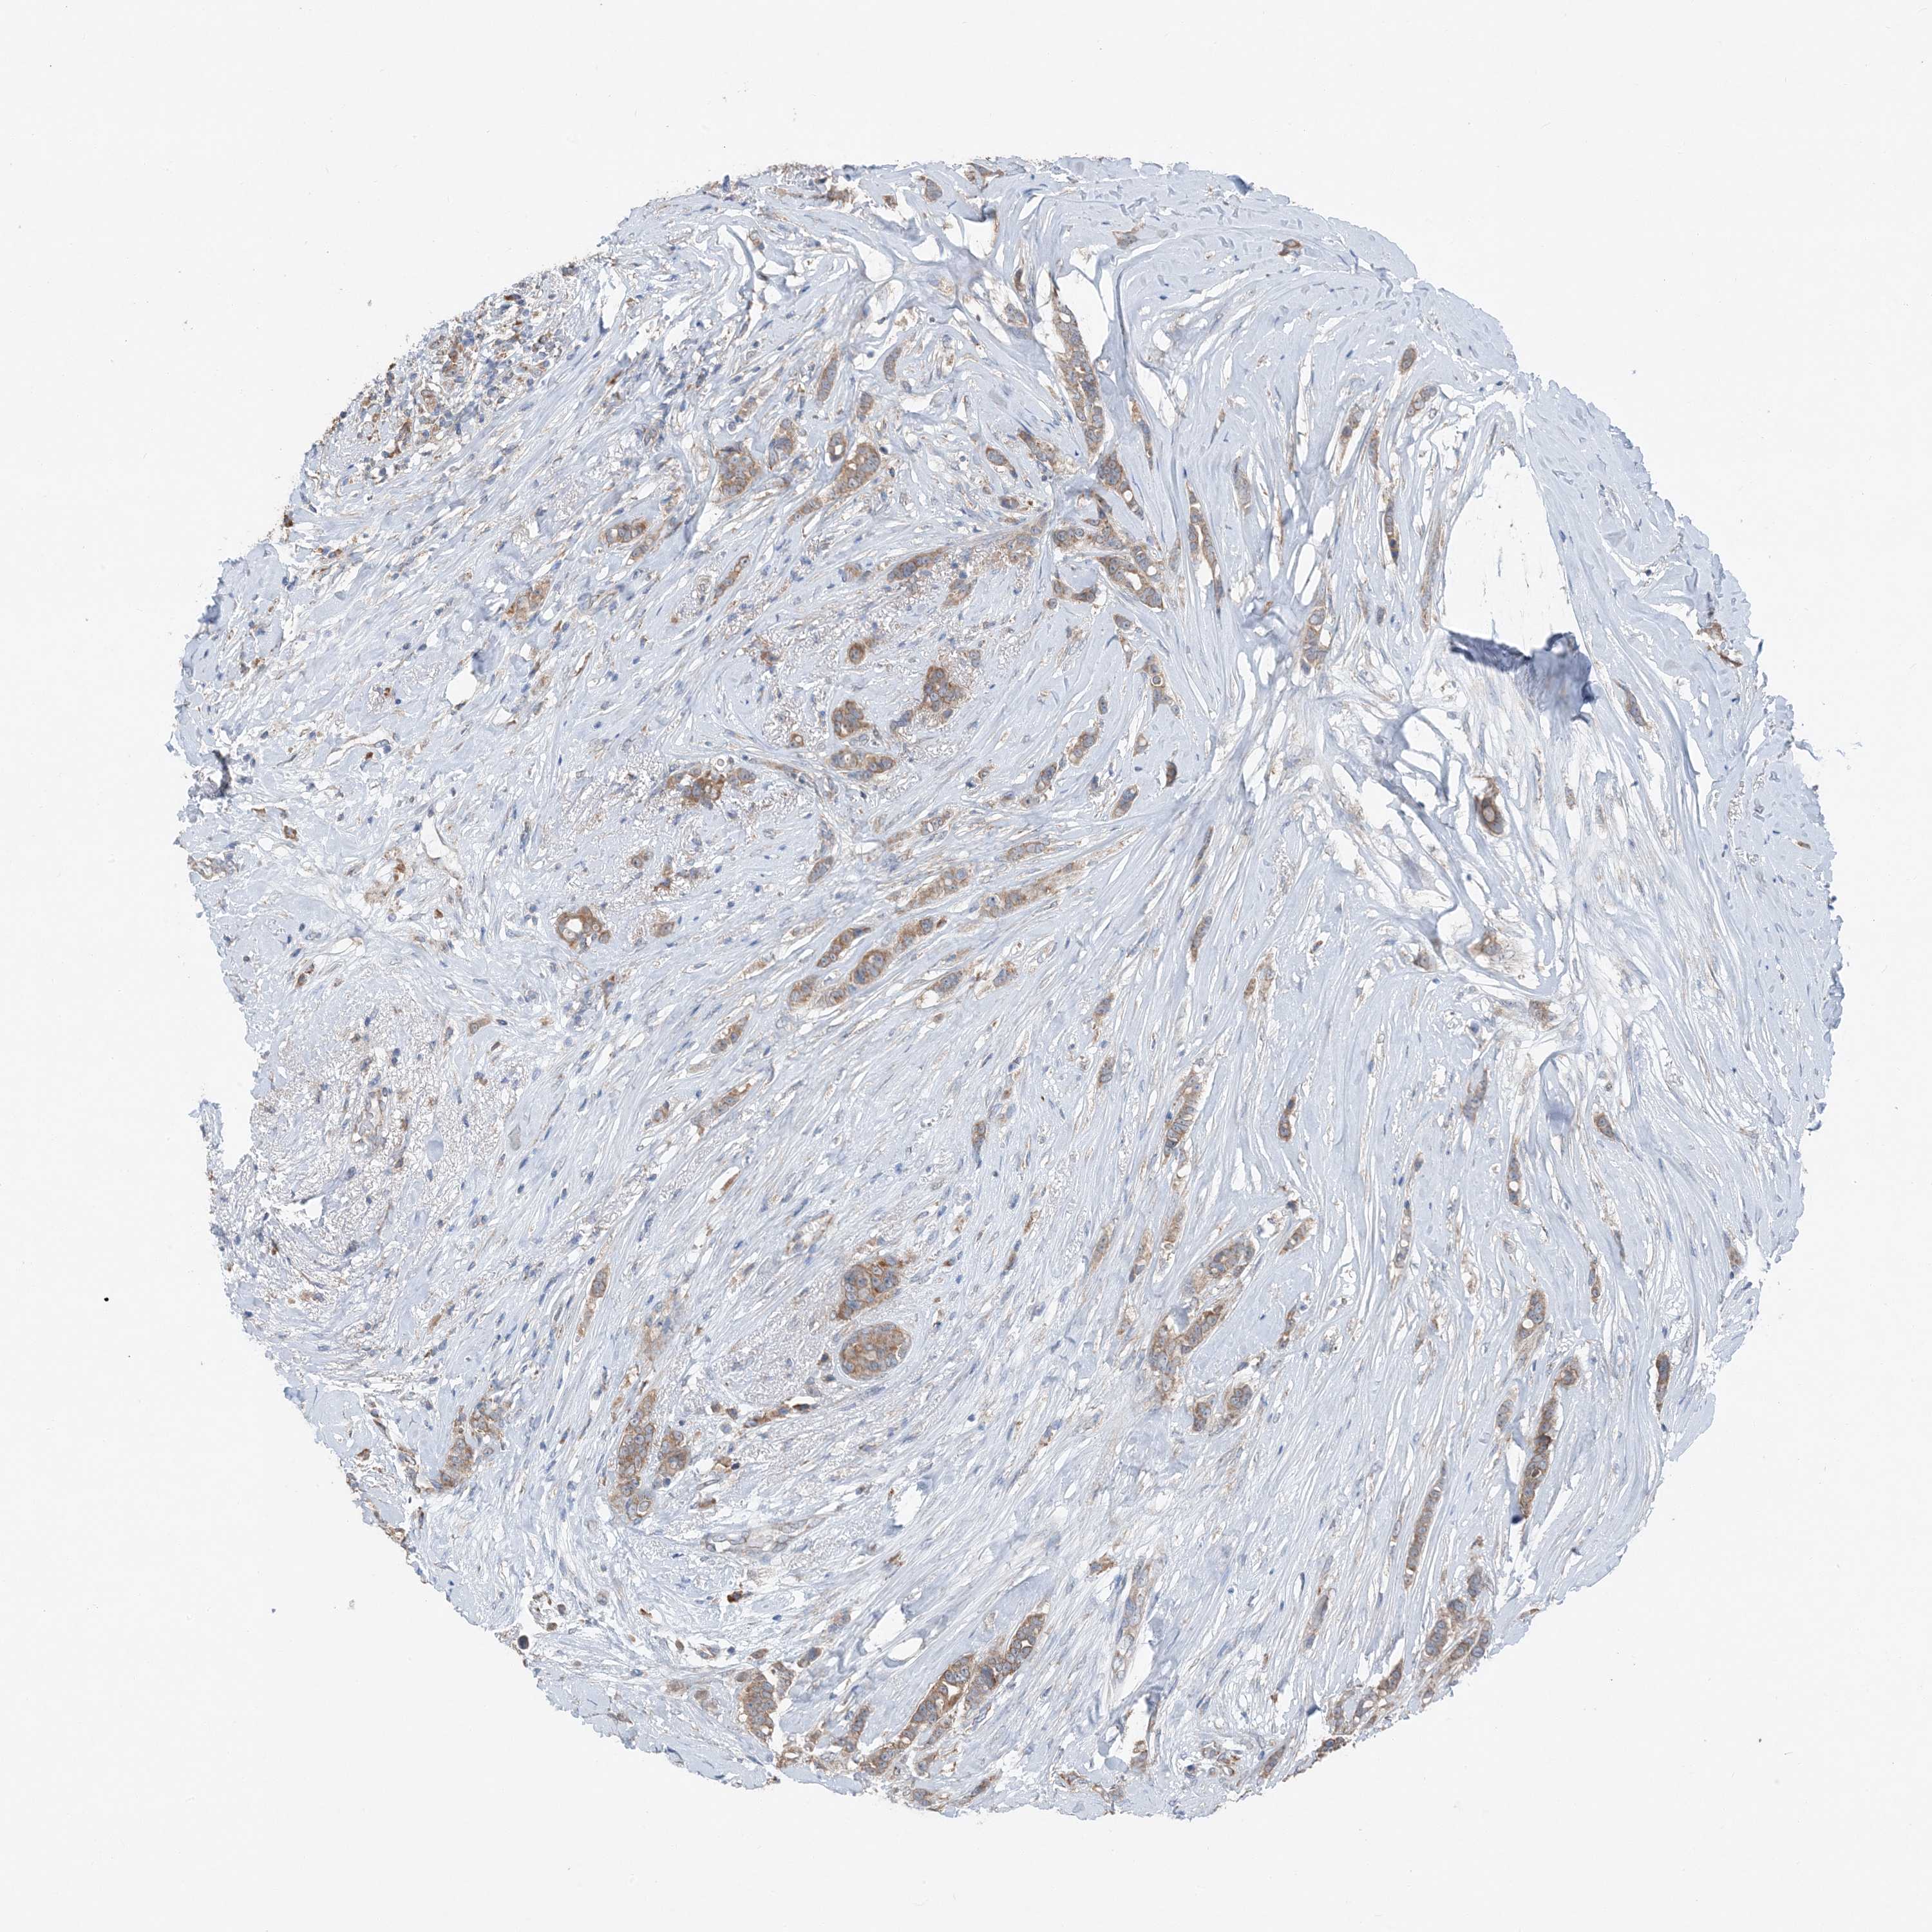

CANCER BREAST CANCER Show tissue menu

BRCA TCGA BRCA VALIDATION PROTEIN EXPRESSION

Breast cancer

Human cancer

DHX30 is not prognostic in Breast Invasive Carcinoma (TCGA)